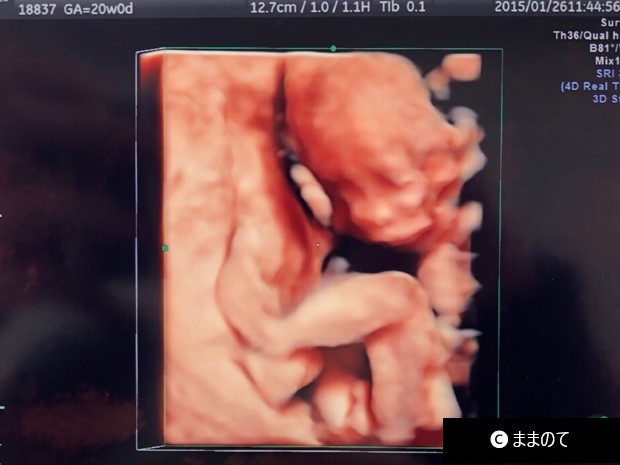

【男の子のエコー】妊娠20週

4Dエコーで撮影された、妊娠20週の胎児です。2本の足の隙間に、はっきりと「おちんちん」と「タマタマ」が映っています。赤ちゃんの姿勢が、おまたが見えやすい姿勢や角度だったこともあり、4Dエコーで鮮明に映すことができました。